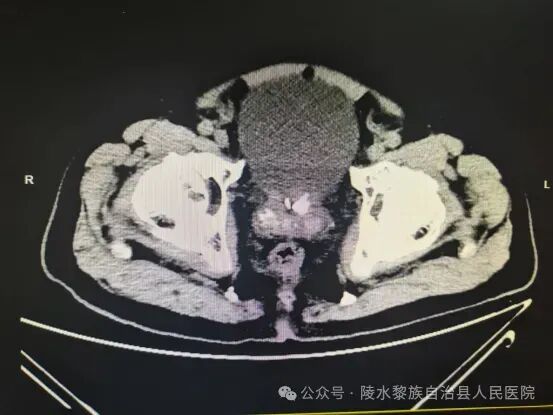

据悉,患者为一位77岁的候鸟老人,在陵水过冬期间遭遇排尿困难长达5小时,并伴有剧烈腹胀及大汗淋漓的症状。于是,该患者紧急前往我院急诊科就医。入院后,急诊科医生虽尝试留置尿管却未果,随即为患者进行了全面细致的检查。CT结果显示,患者左侧输尿管下段存在两枚结石,其中较大者约为0.5×0.6厘米,导致上方尿路积水与扩张;右侧尿路同样呈现积水与扩张状态。膀胱明显充盈,疑似尿潴留,且膀胱腔内存在积气。此外,膀胱内还有结石,最大者约为1.7×0.9厘米;尿道前列腺部也有直径约0.9厘米的结石,同时不排除前列腺钙化的可能性,需结合超声检查进一步确认。前列腺存在钙化灶,左肾还有一颗直径约0.4厘米的小结石。双肾周围伴有少量渗出。

(检查影像图)